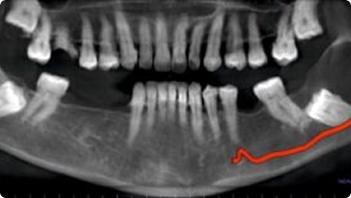

Impacted Tooth

OPG Reporting